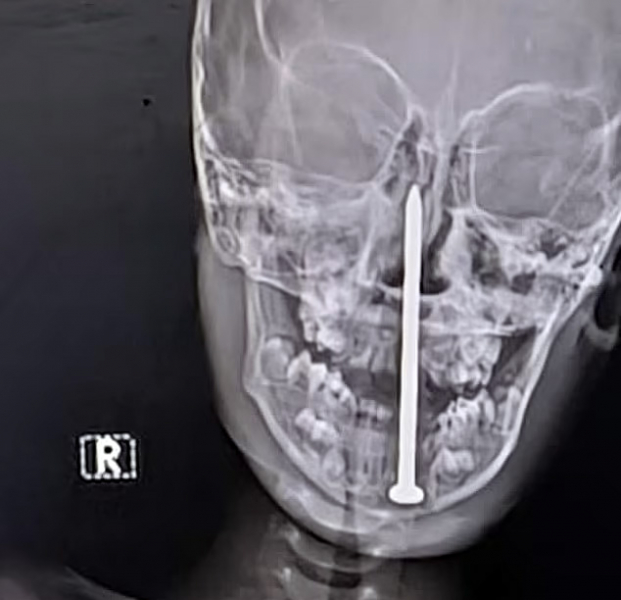

Семилетний мальчик из штата Раджастан перенес сложную нейрохирургическую операцию, во время которой врачи извлекли гвоздь длиной семь сантиметров из его мозга, пишет Daily Mail.

По данным местных СМИ, инцидент произошел, когда мальчик играл рядом со строительной площадкой, где споткнулся и упал носом на гвоздь. Его срочно доставили в больницу в Джайпуре, сделали компьютерную томографию и обнаружили, что инородный предмет почти на пять сантиметров проник в мозговую ткань.

Хирургическая бригада под руководством доктора Санкета Шармы провела более чем четырехчасовую операцию по удалению гвоздя. По словам врачей, чудом затронутыми оказались только лобные доли мозга, отвечающие в основном за когнитивные функции, а не за жизненно важные центры.